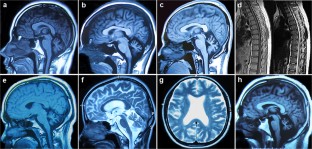

Fig. 1

Fig. 2

Fig. 3